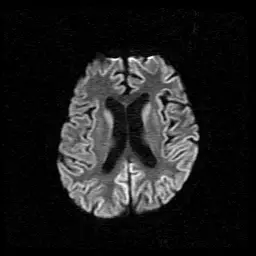

66歲女性最近一個多月來出現記憶力減退、視幻覺、走路不穩,突然聽見鞭炮聲會身體顫抖。她的腦部磁振造影擴散加權成像(diffusion-weighted imaging)結果如下圖。她最可能的診斷是:

聚焦於Creutzfeldt–Jakob disease(CJD)這種人類朊病毒(prion)疾病所致的快速進展性失智,其典型臨床症狀包含迅速惡化的認知功能、視幻覺、共濟失調及聲響引發的肌陣攣,再搭配MRI DWI序列可見的「皮質絲帶狀高訊號(cortical ribboning)」做為診斷依據。

從所提供的axial DWI影像可見:

- 兩側大腦皮質沿著腦回呈廣泛的高訊號,形態類似皮質絲帶(gyriform ribbon),散布於多個腦回區域。

- 皮質內訊號明顯,而白質未見對應高訊號,符合受限擴散特徵。

- 未見典型的梗塞區域(如區域性餵流血管分布),也無多發稀疏小梗塞或髓鞘病變。

這種對稱性、廣泛的皮質限制性擴散改變正是sCJD於DWI最敏感的影像表現,常稱為「cortical ribboning」或伴隨基底節之高訊號(radiologica.org)。